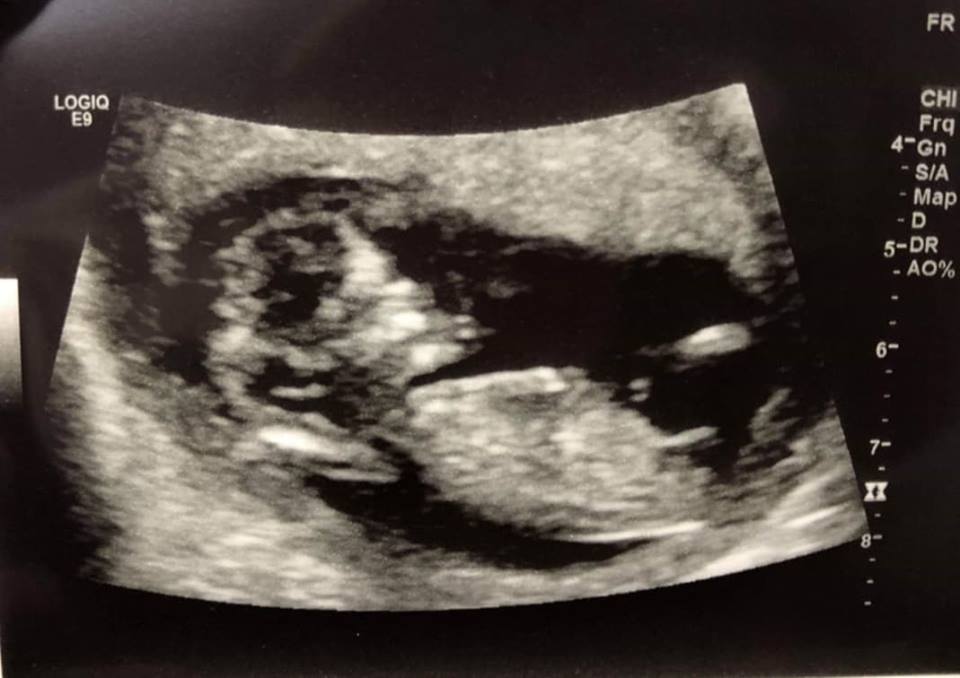

Attachment 40735 11 weeks 6 days

Too early. Nubs are the same at this point so closer to 13 weeks is better.

Still too early but nub might be on the rise so ever so slight boy lean from me.